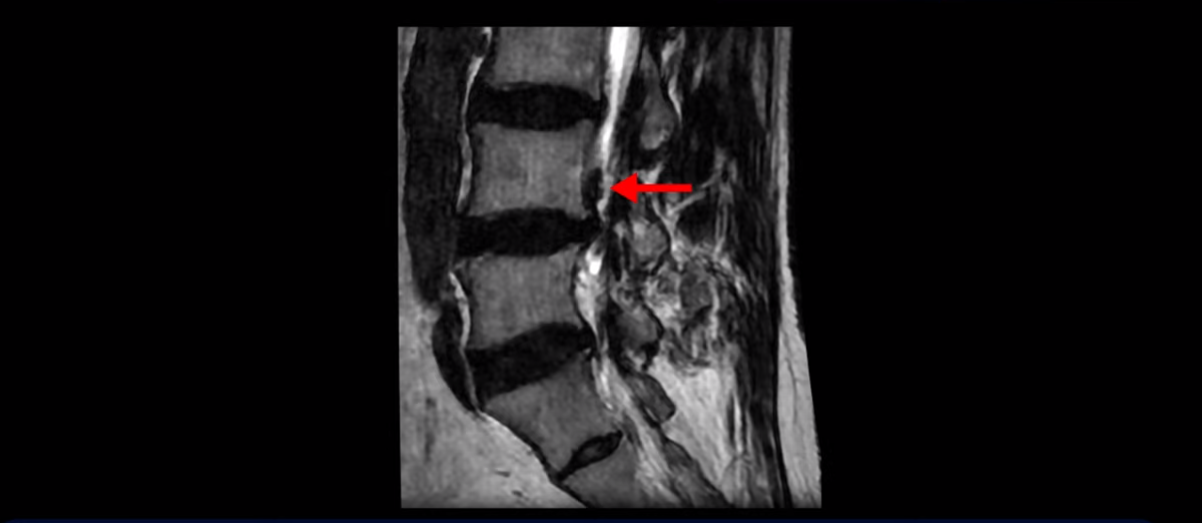

이분 MRI를 보면 허리 세 마디 정도의 퇴행성 디스크가 있고

4번 5번 마디에는 중심성 협착이 있습니다.

후관절과 황색인대가 두꺼워져 있어서 척추관이 좁아져 있습니다.

하지만 이분의 갑작스러운 통증을 일으키는 원인은 4번 5번에 발생한 디스크 파열입니다.

이분은 왼쪽 무릎 아래로 본인 표현으로는 다리를 잘라 버리고 싶다고 할 정도의 심한 통증이 있는데 보통 이런 표현은 디스크 파열이 발생했을 때 많이 사용하는 표현입니다. 이분 4번 5번 디스크를 자세히 보면 왼쪽으로 파열되어 밀려 올라간 디스크 수핵을 볼 수 있습니다.

옆에서도 보이지만 단면에서도 왼쪽으로 심하게 밀려나온 수핵이 잘 보입니다.